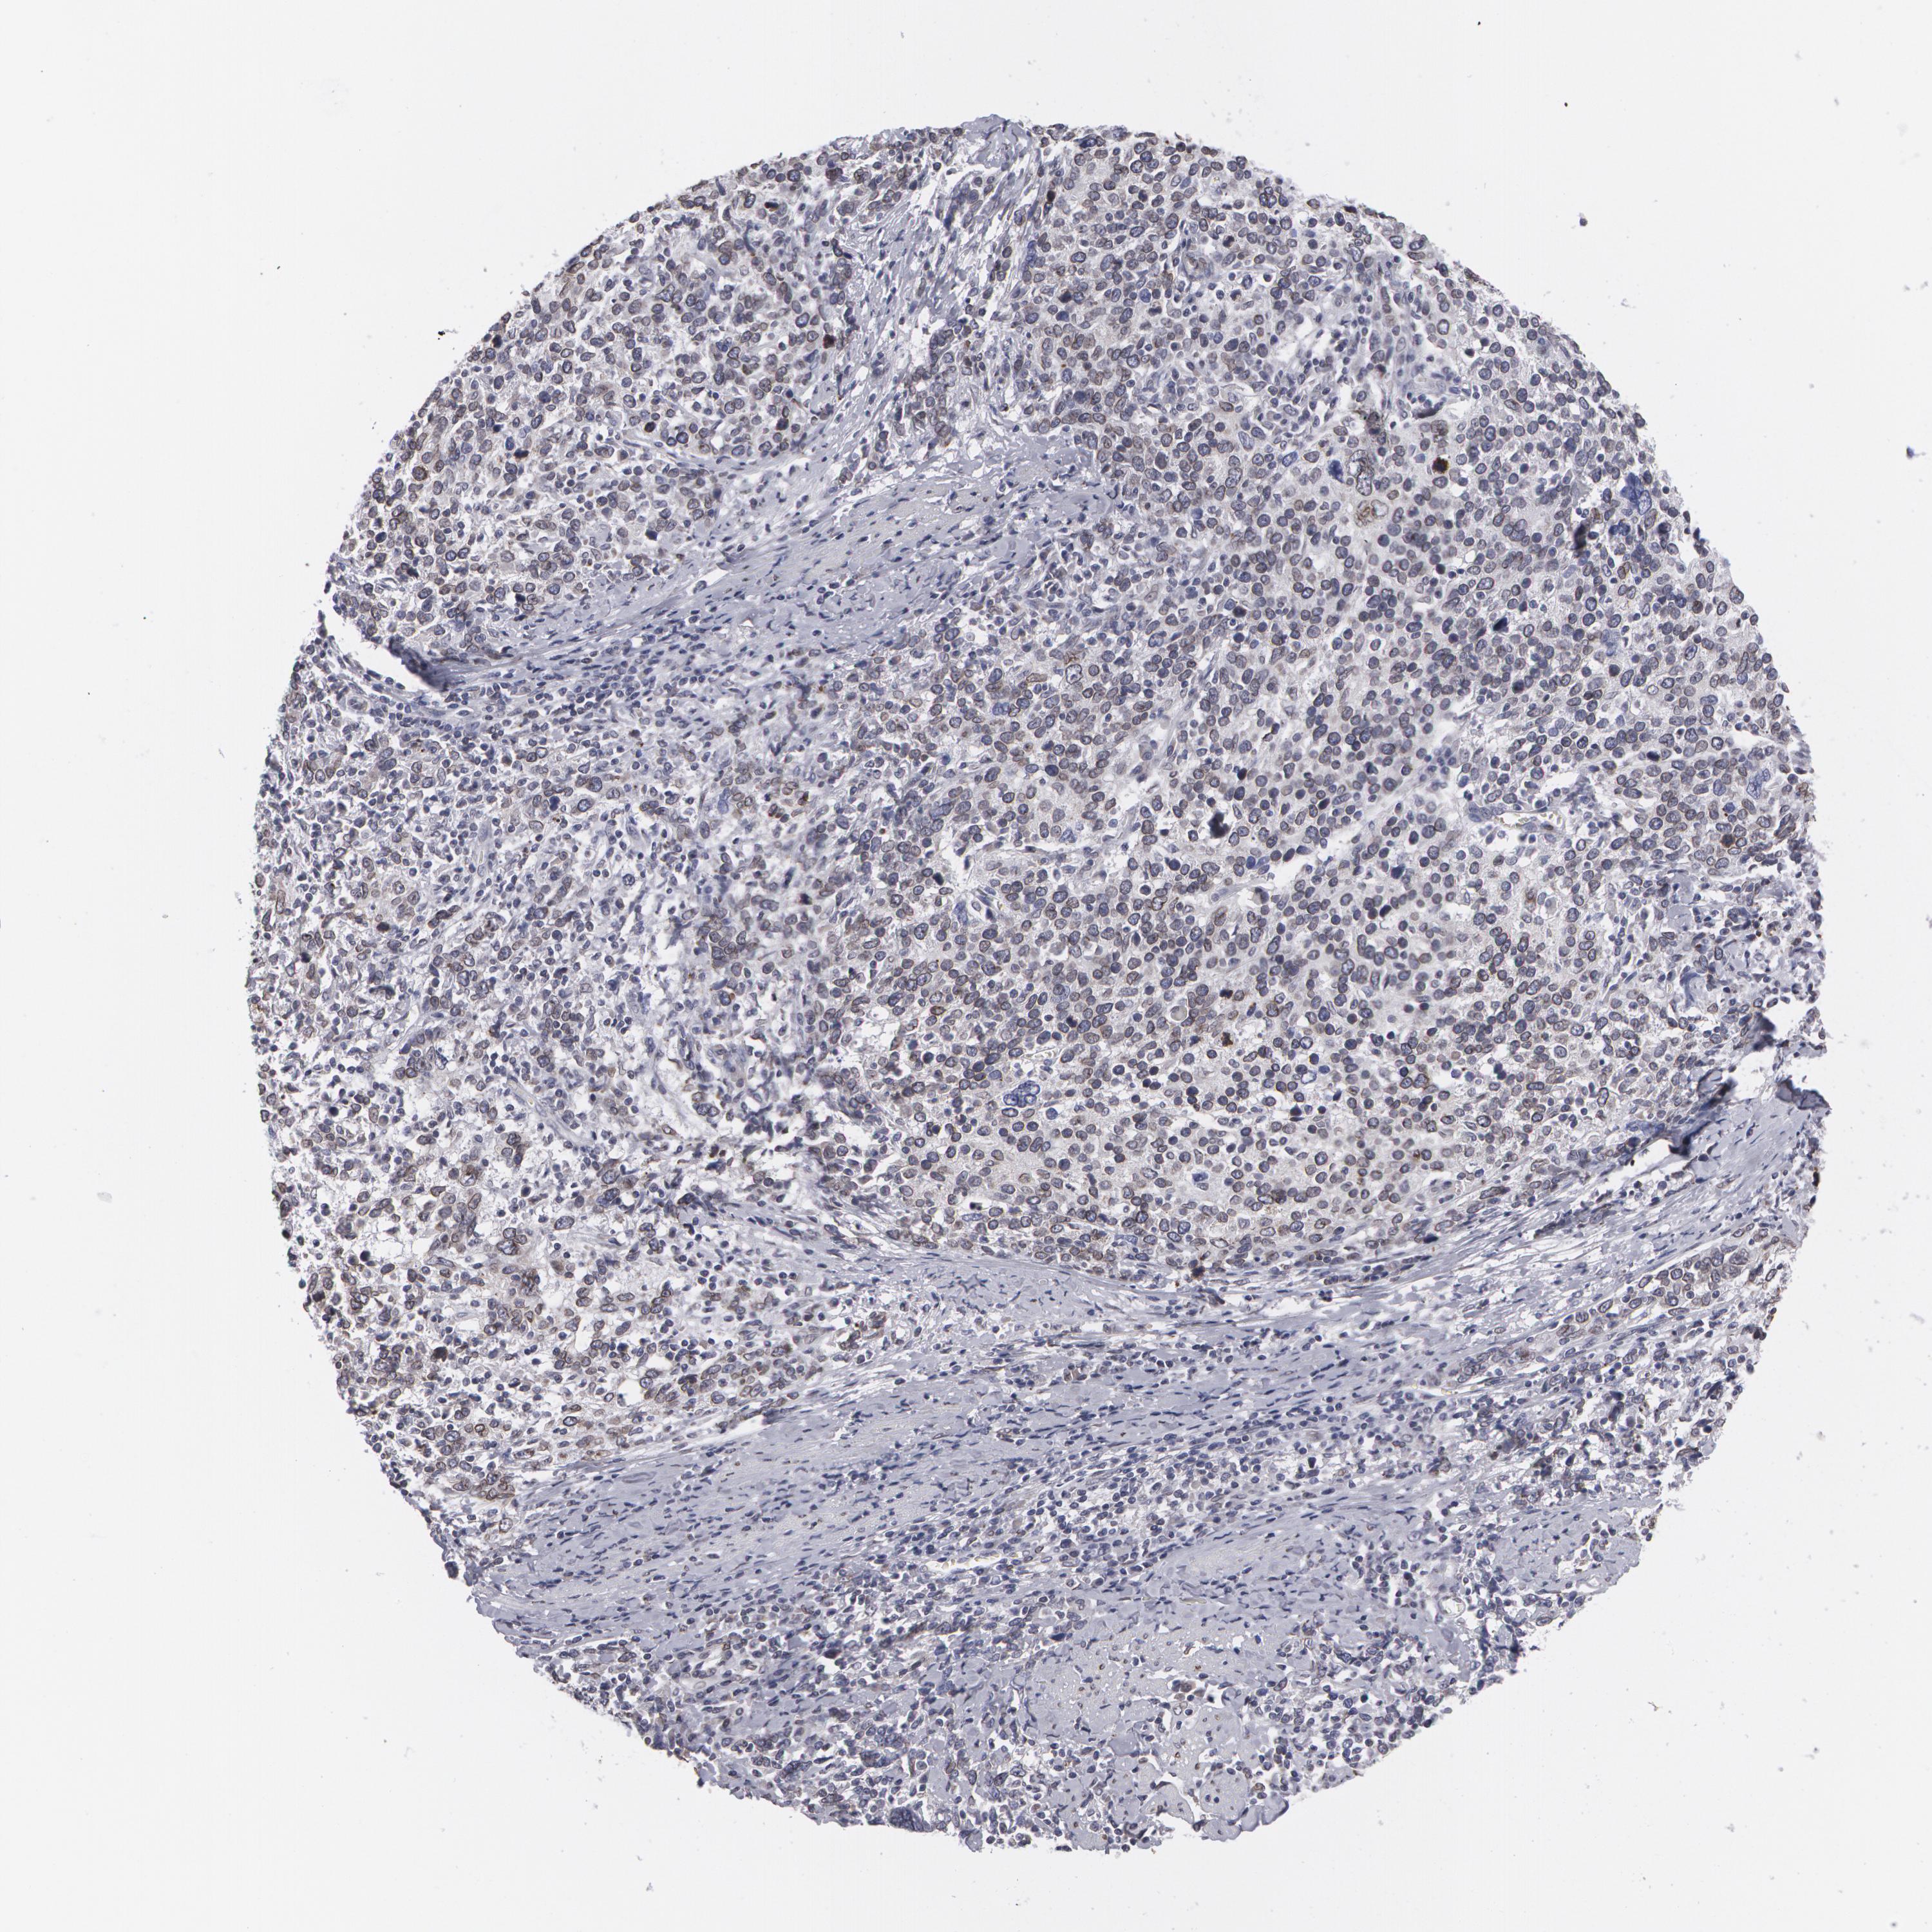

CERVICAL CANCER - Protein expressioni

A mouse-over function shows sample information and annotation data. Click on an image to view it in a full screen mode. Samples can be filtered based on level of antibody staining by selecting one or several of the following categories: high, medium, low and not detected. The assay and annotation is described here.

Note that samples used for immunohistochemistry by the Human Protein Atlas do not correspond to samples in the TCGA dataset.

Antibody stainingi

Antibody staining in the annotated cell types in the current human tissue is reported as not detected, low, medium, or high, based on conventional immunohistochemistry profiling in selected tissues. This score is based on the combination of the staining intensity and fraction of stained cells.

Each image is clickable and will lead to virtual microscopy that enables deeper exploration of all samples and also displays staining intensity scores, fraction scores and subcellular localization as well as patient and tissue information for each sample.

Antibody HPA000609

Antibody CAB001545

Antibody CAB002029

Antibody CAB062552

Adenocarcinoma, NOS